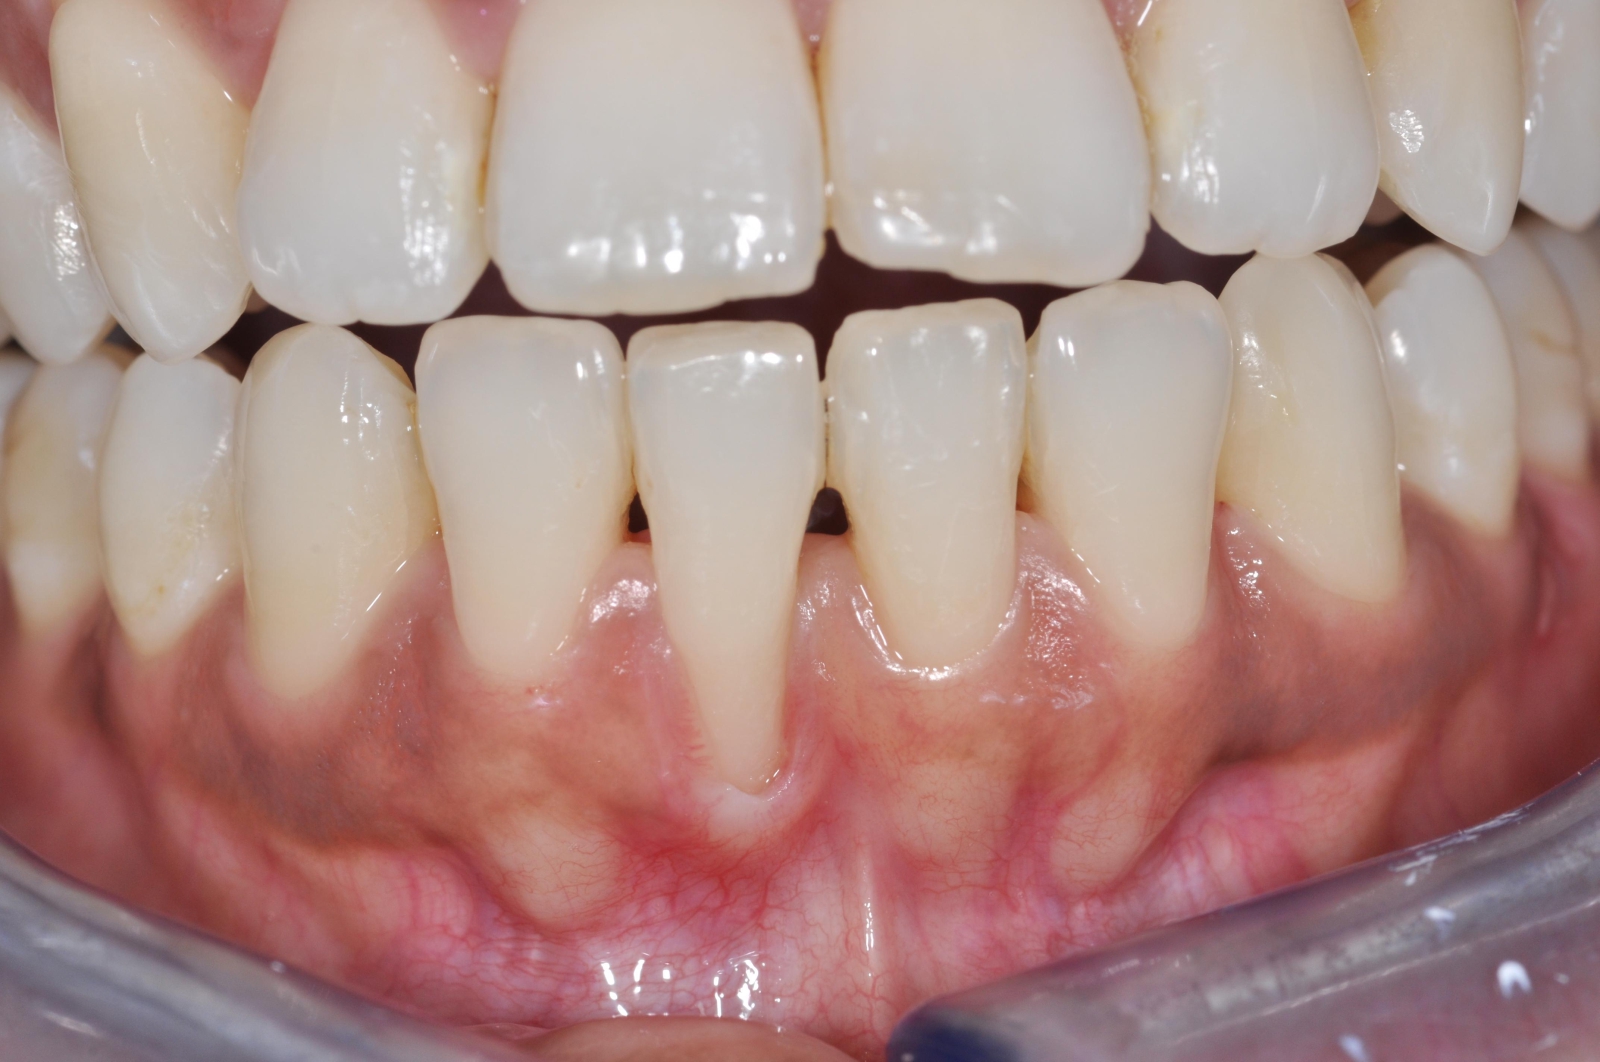

Le sourire gingival est appelé Gummy Smile. Il s’agit d’une situation lors de laquelle la gencive descend trop bas sur les couronnes des dents, soit les parties qui sont normalement visibles lorsqu’on sourit.

Cela se traduit par des gencives proéminentes et des dents qui semblent plus courtes. Bien entendu, cela nuit à l’apparence du sourire.